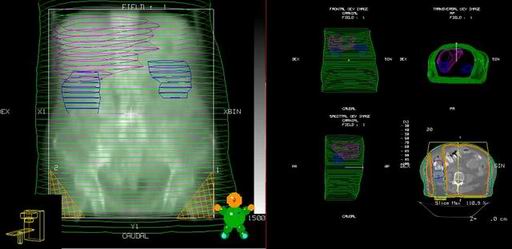

Teleterapie I

- Vysokoenergetické fotonové záření nad 4 MeV (lineární urychlovač event. Co-60 s možností izocentrického ozařování)

- Zaměření pomocí simulátoru

- 3D plánování, využití CT

- Techniky více polí, možnost vykrývání (MLC, individuální bloky)

- Možnost kontroly (portal vision, kobaltogram, dozimetrie)

Teleterapie II

- Plánovací cílový objem základní: malá pánev po horní okraj L5

- Plánovací cílový objem rozšířený: N+zevní ilické a

hypogastrické - horní okraj L4

N+společné ilické, paraaortální - dolní okraj Th 12 - Dávka na m.p. 44,0-50,0 Gy/5x týdně/1,8-2,0Gy